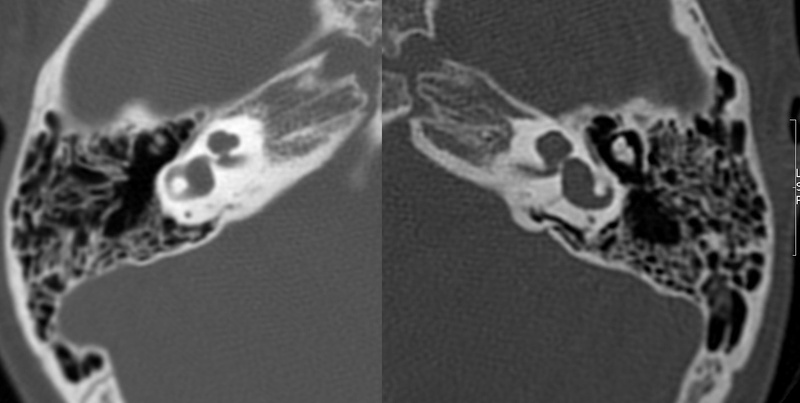

El estudio de imagen se realizó mediante TC de oídos y mastoides. Se aplicaron en cuatro pacientes varones y una madre oyente considerada portadora. Los estudios se clasificaron según Sennanoğlu y cols. [8,9,13].

Evaluación de Imagen (TC)

Los hallazgos radiológicos, mediante TC de oídos a cuatro pacientes varones y una madre oyente, portadora obligada, se analizaron y clasificaron según Sennanoğlu et al. [8,9]. En ese sentido, son consistentes con PI-III en tres de ellos: IV-1, IV -2 y IV- 4. El paciente IV-3 mostró PI-I; la madre portadora obligada no mostró alteración alguna (Ver Tabla 3). En los cuatro pacientes estudiados de esta familia observamos dos tipos de MOI, PI-I y PI-III, incluso entre los hermanos IV-2 y IV-3, que presentaron diferente tipo de PI, lo que evidencia expresividad variable. La malformación PI-III es de las MOI menos frecuente y se encuentra presente en este estudio familiar como predominante.

IV-1. PI-III. HNS severa derecha con curva de perfil irregular, HNS profunda izquierda, con restos auditivos, congénita.

IV-2. PI-III. HNS profunda bilateral con curvas de perfil plano, congénita.

IV-3. PI-I. HNS media bilateral, congénita.

IV-4. PI-III. HNS profunda bilateral, con curva de perfil irregular derecha y plana izquierda, congénita.